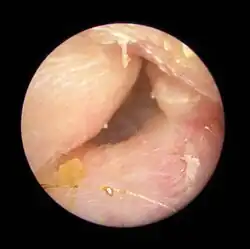

Exostoses in the ear canal, as seen through otoscopy

Surfer's ear is the common name for an exostosis or abnormal bone growth within the ear canal. They are otherwise benign hyperplasias (growths) of the tympanic bone thought to be caused by frequent cold-water exposure.[1] Cases are often asymptomatic.[1] Surfer's ear is not the same as swimmer's ear, although infection can result as a side effect.

Irritation from cold wind and water exposure causes the bone surrounding the ear canal to develop lumps of new bony growth which constrict the ear canal. Where the ear canal is actually blocked by this condition, water and wax can become trapped and give rise to infection. The condition is so named due to its high prevalence among cold water surfers, although it can occur in any water temperature due to the evaporative cooling caused by wind and the presence of water in the ear canal.